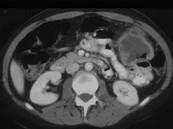

问题 男,55岁,腹部胀痛不适1月余,CT检查如图,最可能的诊断是()

选项 A.结肠结核 B.结肠淋巴瘤 C.结肠转移瘤 D.假膜性结肠炎 E.横结肠癌

答案 E